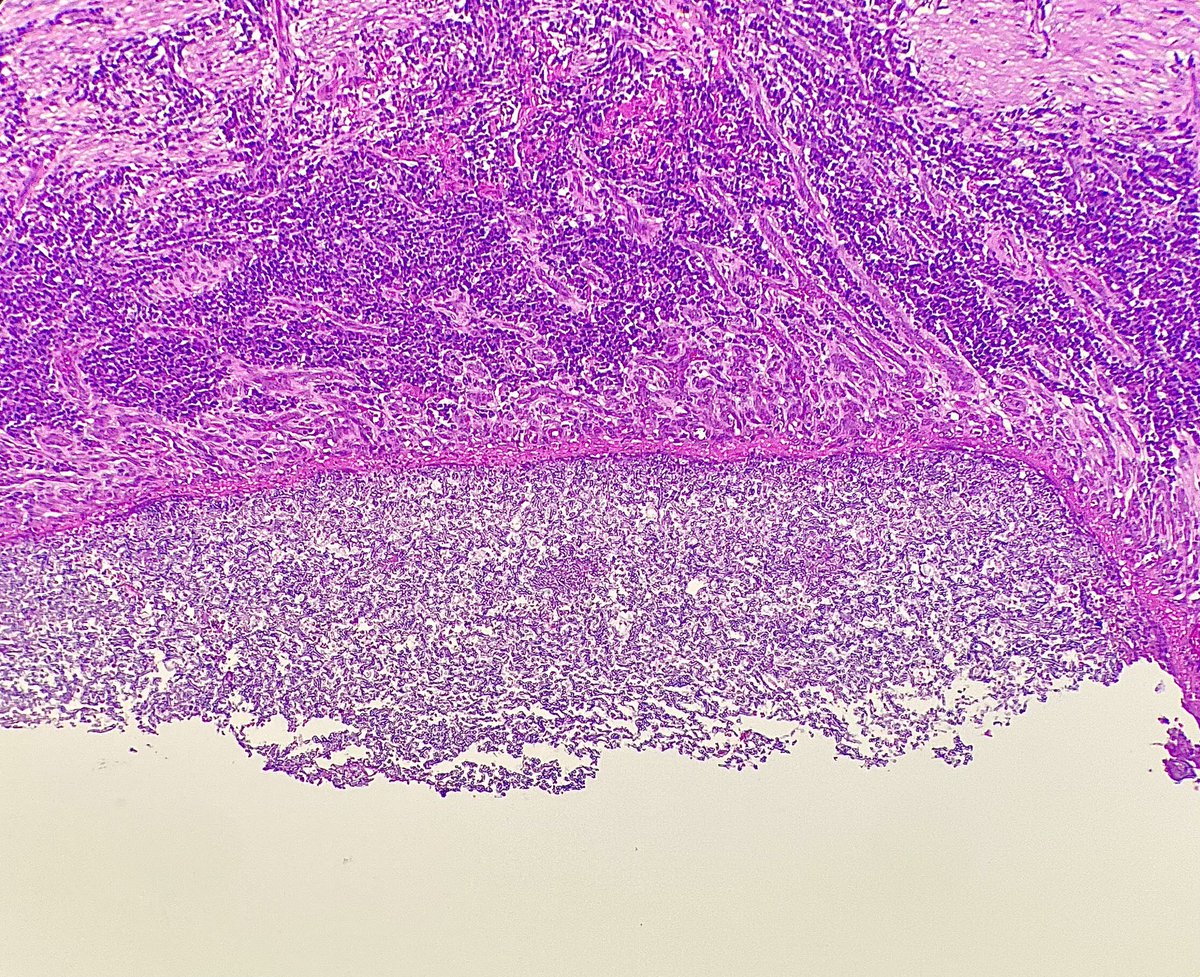

THE WAY PATHOLOGY BOOKS SHOULD BE IN THE 21ST CENTURY-SIMULATING MULTIHEAD SCOPE TEACHING USING THE BIGGEST MULTIHEAD SCOPE IN THE WORLD-PATHPRESENTER Thanks to AceMyPath team for the great effort put in to create a spectacular print book with annotated WSI for every diagnosis.

Pathology trainees/budding pathologists take note: #AceMyPath team is soon releasing a surgical pathology boards review book like none other "ACE THE BOARDS: SURGICAL PATHOLOGY REIMAGINED" Here is a glimpse of what is to come! #Happylearning @AceMyPath @AkankshaGuptaMD